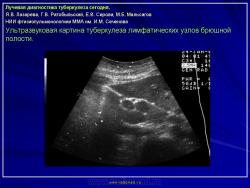

Лучевая диагностика туберкулеза сегодня

Я.В. Лазарева, Г.В. Ратобыльский, Е.В. Серова, М.Б. Мальсагов

НИИ фтизиопульмонологиии ММА им. И.М. Сеченова